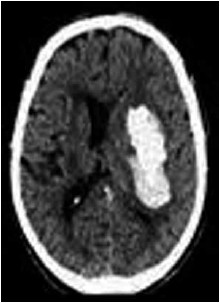

Paciente de 57 anos, masculino, hipertenso sem controle adequado, é admitido na emergência com quadro de hemiplegia súbita à esquerda e disartria. Na admissão, apresenta Glasgow de 13, afebril, pressão arterial aferida de 200/130 mmHg e glicemia capilar de 87 mg/dL. Tomografia de crânio abaixo.

Assinale a alternativa correta referente ao tratamento inicial para este paciente.